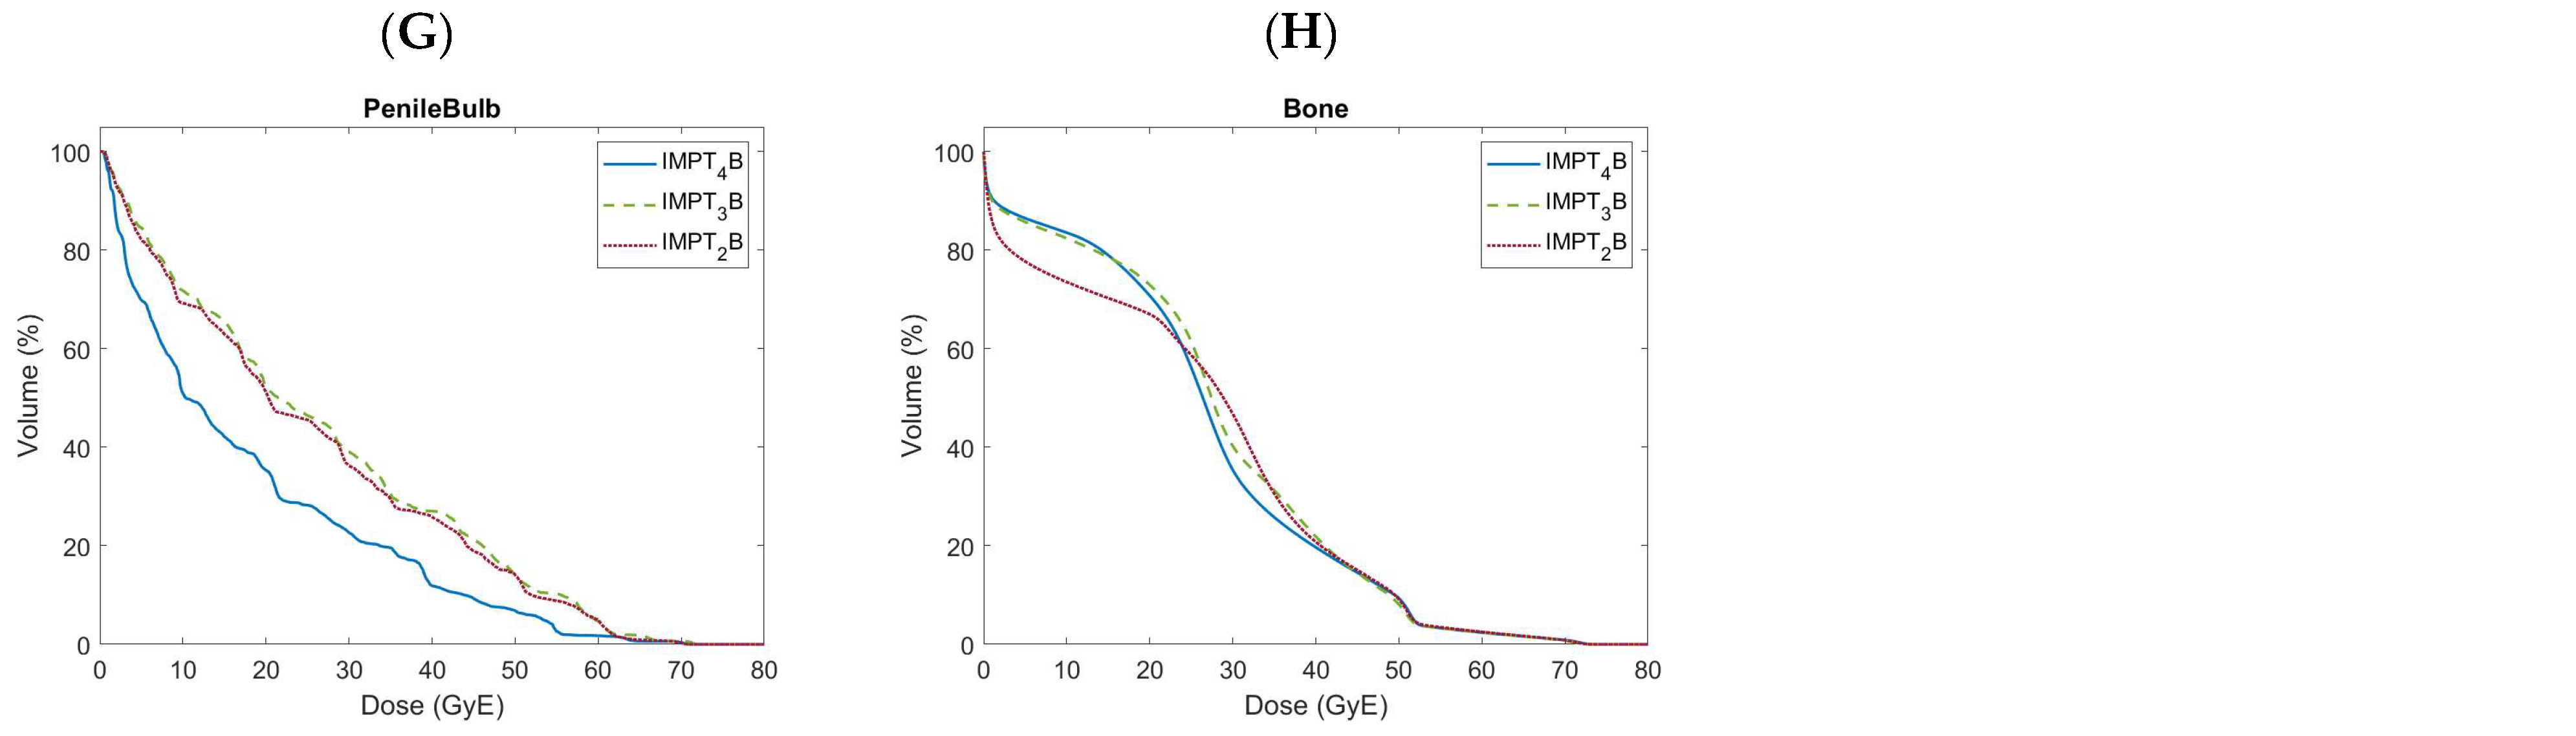

| Penile Bulb | Mean < 52.5 GyE | 23.6 | 6.2 | 23.7 | 7.3 | 22.0 | 6.6 | 0.848 | 0.003 | <0.001 |

| Bone | V 10.0 GyE < 90.0% | 73.5 | 5.1 | 82.4 | 5.0 | 83.4 | 3.4 | <0.001 | <0.001 | 0.027 |

| V 40.0 GyE < 37.0% | 20.8 | 4.9 | 21.8 | 3.9 | 19.6 | 3.3 | 0.163 | 0.060 | 0.000 | |

| Mean Dose (GyE) | 26.0 | 2.5 | 27.5 | 2.1 | 26.6 | 1.9 | 0.001 | 0.038 | 0.001 | |

3.5. Bony Organs at Risk

3.6. Other Organs at Risk